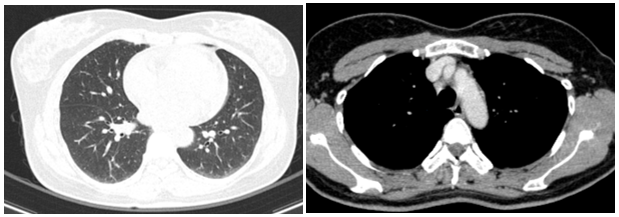

Cắt lớp vi tính lồng ngực:

Hình 2: Hình ảnh cắt lớp vi tính lồng ngực chưa phát hiện bất thường

Cắt lớp vi tính ổ bụng:

Hình 3: Hình ảnh cắt lớp vi tính ổ bụng chưa phát hiện bất thường